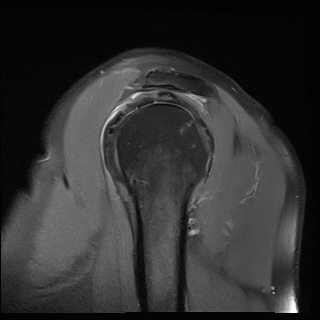

ÀÚ±â°ø¸í°Ë»ç

±Ø»ó°Ç ÆÄ¿­, Á¡¾×³¶¿°, °ßºÀÇÏ °ñ±Ø

¹æ»ç¼±»çÁøÀ̳ª ÀÚ±â°ø¸í°Ë»ç¿¡¼­ °ñ±ØÀÌ °üÂûµÇ°í ±Ø»ó°Ç ÆÄ¿­ÀÌ ÀÖ´Â °æ¿ì °Ë»ç¿¡¼­ º¸ÀÌ´Â

°ñ±ØÀÌ ±Ø»ç°ÇÆÄ¿­ÀÇ ¿øÀÎÀ̶ó°í ÃßÁ¤ÇÒ ¼öµµ ÀÖ´Ù.  ±×·¯³ª ±Ø»ó°ÇÆÄ¿­ÀÌ Ç¥Ãþº¸´Ù´Â ½ÉÃþ¿¡¼­

´õ ¸¹ÀÌ ¹ß»ýÇϰí Áõ»óÀ» ÀÏÀ¸Å°Áö ¾Ê´Â °ñ±ØÀÌ ¸¹Àº Á¡À» °í·ÁÇÒ ¶§ °Ë»ç¿¡¼­ º¸ÀÌ´Â °ñ±ØÀ»

Ä¡·á(°ßºÀ¼ºÇü¼ú)ÀÇ ´ë»óÀ¸·Î ÇÏ´Â °ÍÀº Çϸ®ÀûÀÎ °áÁ¤ÀÌ ¾Æ´Ï´Ù. ÀÌ È¯ÀÚÀÇ °æ¿ìó·³ ±Ø»ó°Ç

³»ÃøÀÇ ºÎÁ¾°ú Ç¥Ãþ ¶Ç´Â ÀüÃþ ÆÄ¿­ÀÌ ÀÖÀ¸¸é¼­ Á¡¾×³¶ÀÇ ºÎÁ¾°ú Ãæµ¹°Ë»ç ½Ã Ãæµ¹ ¼Ò°ßÀ» º¸ÀÌ´Â °æ¿ì¿¡

¹æ»ç¼±À̳ª ÀÚ±â°ø¸í°Ë»ç¿¡¼­ º¸ÀÌ´Â °ñ±ØÀÌ ±Ø»ó°Ç ÆÄ¿­ÀÇ ¿øÀÎÀ¸·Î ÃßÁ¤ÇÒ ¼ö ÀÖ´Ù.